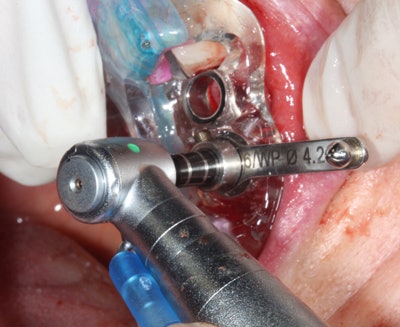

Flapless guided implant surgery only requires tissue punch to access the available bone (figures 3 and 4). When ample keratinized tissue is present and sufficient bone volume is present, sutures are unnecessary and the surgery is minimally invasive.

Figure 3: Workflow-guided implant.